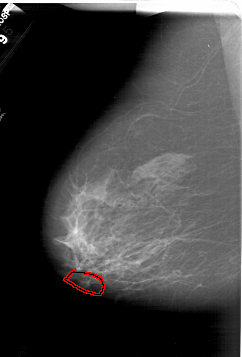

A_1386_1.LEFT_MLO

LEFT_MLO LINES 6421 PIXELS_PER_LINE 4351 BITS_PER_PIXEL 12 RESOLUTION 43.5 OVERLAY

FILE: A_1386_1.LEFT_MLO.OVERLAY

TOTAL_ABNORMALITIES 1

ABNORMALITY 1

LESION_TYPE CALCIFICATION TYPE AMORPHOUS DISTRIBUTION LINEAR

ASSESSMENT 4

SUBTLETY 1

PATHOLOGY BENIGN

TOTAL_OUTLINES 1

BOUNDARY